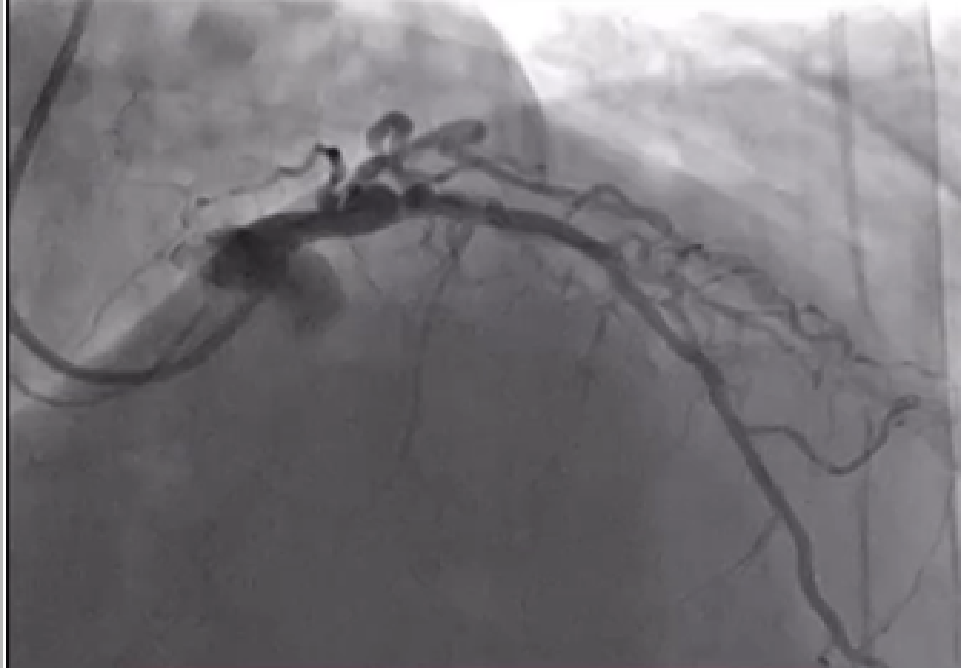

Diagnostic angiography has been performed and occluded Left Anterior descending artery was visualized but, the right coronary artery couldn't be find from the right coronary ostium. 6F EBU 3.5 catheter trough the right radial approach has been inserted and we could visualize right coronary artery arising from the left coronary ostia. Direct stenting was performed with 3.5/38mm DES at 17 atm. After this procedure we continued to LAD, passed the occlusion with BMW wire after which predilatation with 2.5/20 mmx 14 atm has been performed and after that 3.0/28mm DES at 15atm was implanted with good end result

MOVIE-0011.mp4

MOVIE-0021.mp4

MOVIE-0022.mp4